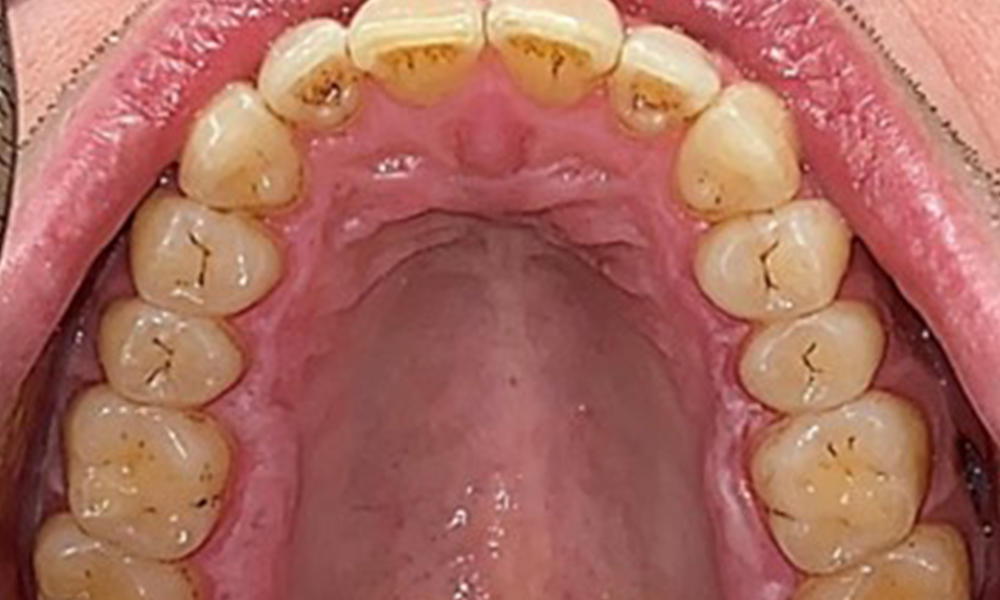

Occlusal view of the maxilla.

Fig. 3: Occlusal view of the maxilla, © Dr R. Krapf

Extraoral and intraoral findings

There were no pathological extraoral findings. During intraoral examination, inspection of the frontal view revealed brownish discolouration near the keratinised gingiva and at the transition to the moveable mucosa (Fig. 2), which could be attributed to nicotine consumption. Whitish mucosal lesions were observed on the palate, particularly near the maxillary molar palatal surfaces, indicating increased keratinisation and can also be attributed to nicotine consumption. The tongue was covered with a removable white and brownish coating.

Dental findings

The patient has full dentition with a total of 28 teeth. There were noteworthy erosions and attritions. (Fig. 4, Fig. 5). Due to bruxism, the patient has been wearing a splint with an adjusted bite block at night for many years. The erosions were caused by long-term consumption of isotonic beverages. No periodontal bone loss or active caries were observed.